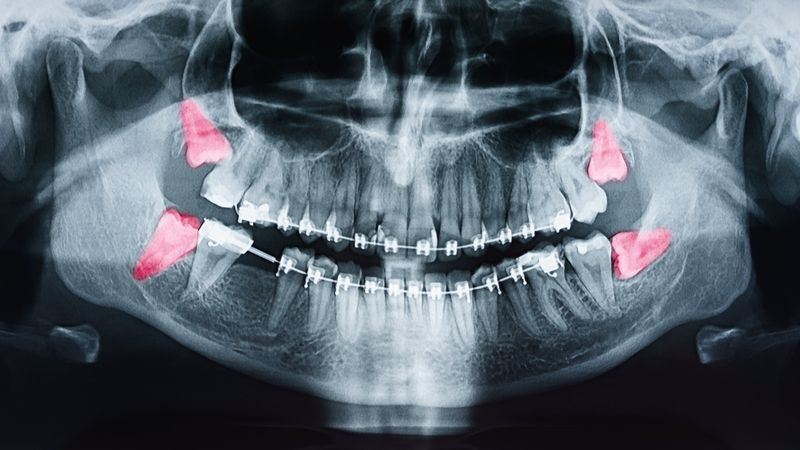

The ideal candidate for wisdom tooth extraction is determined primarily through dental X-rays. This imaging technique enables Dr. Amara Collett and her team at Boutique for Cosmetic Dentistry to identify any impacted teeth and strategize the best extraction method. If you're experiencing discomfort, it's advisable to schedule an appointment as soon as possible. Early treatment ensures a smoother, more predictable outcome.

Beginning with an in-depth consultation and thorough examination, our team captures x-rays of your teeth to assess the necessity of the procedure. On the day of the procedure, a sedative of your choice is administered to ensure comfort. An incision is made to access and extract the problematic wisdom tooth, after which the site is sutured. This process is replicated for any other wisdom teeth needing removal. Although some pain and swelling are expected post-surgery, the question often arises: how long does pain after wisdom tooth extraction last? Typically, discomfort and swelling peak within the first few days but steadily decrease thereafter. It's important to follow post-op care instructions to ensure a swift and smooth recovery.